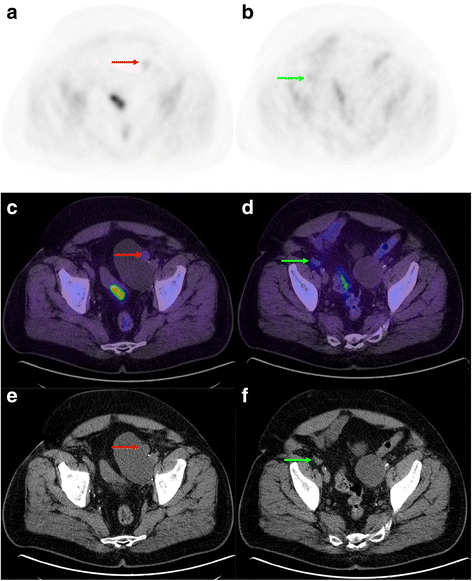

Restaging FCH-PET/CT in a 68 y.o. patient with biochemical relapse following radical prostatectomy. Initially, PCa Gleason sum was 7. PSA was 0.35 mg/L at time of examination. Whole-body MIP (a) and transaxial fusion slices (b, c) showed two foci of moderate uptake in the right iliac nodal area (red arrows) that were initially perceived as suspicious for nodal relapse. However, dynamic PET MIP (d) and fusion series (e) showed no early focal activity at either site, which was consistent with urinary activity on the whole-body scan. This study was interpreted as negative and the patient underwent salvage radiotherapy

In the presence of multiple hyperactive lesions, it is the pattern of dissemination thereof, rather than their level of uptake, which is most critical to determine the probability of metastasis. However, in the presence of a solitary lesion in an area consistent with metastatic spread (e.g. external iliac node ipsilateral to the dominant primary lesion), the level of uptake may have more weight in the diagnostic decision-making process. If the uptake of such lesion were only faint, it would be classified as more likely benign. Figure 6 illustrates a case of bilateral pelvic nodes with faint uptake, which were interpreted as likely negative.

Restaging FCH-PET/CT in a 68 y.o. patient with biochemical relapse following radical prostatectomy. Initially, PCa Gleason sum was 8. PSA was 0.48 mg/L at time of examination. Transaxial PET (a, b), fusion (c, d) and CT (e, f) slices showing faint activity in left paravesical (red arrows) and right external iliac (green arrows) enlarged lymph nodes. However, the very low uptake in the latters was suggestive of a benign process, such as inflammatory or reactive nodes. This study was interpreted as negative and the patient underwent salvage radiotherapy